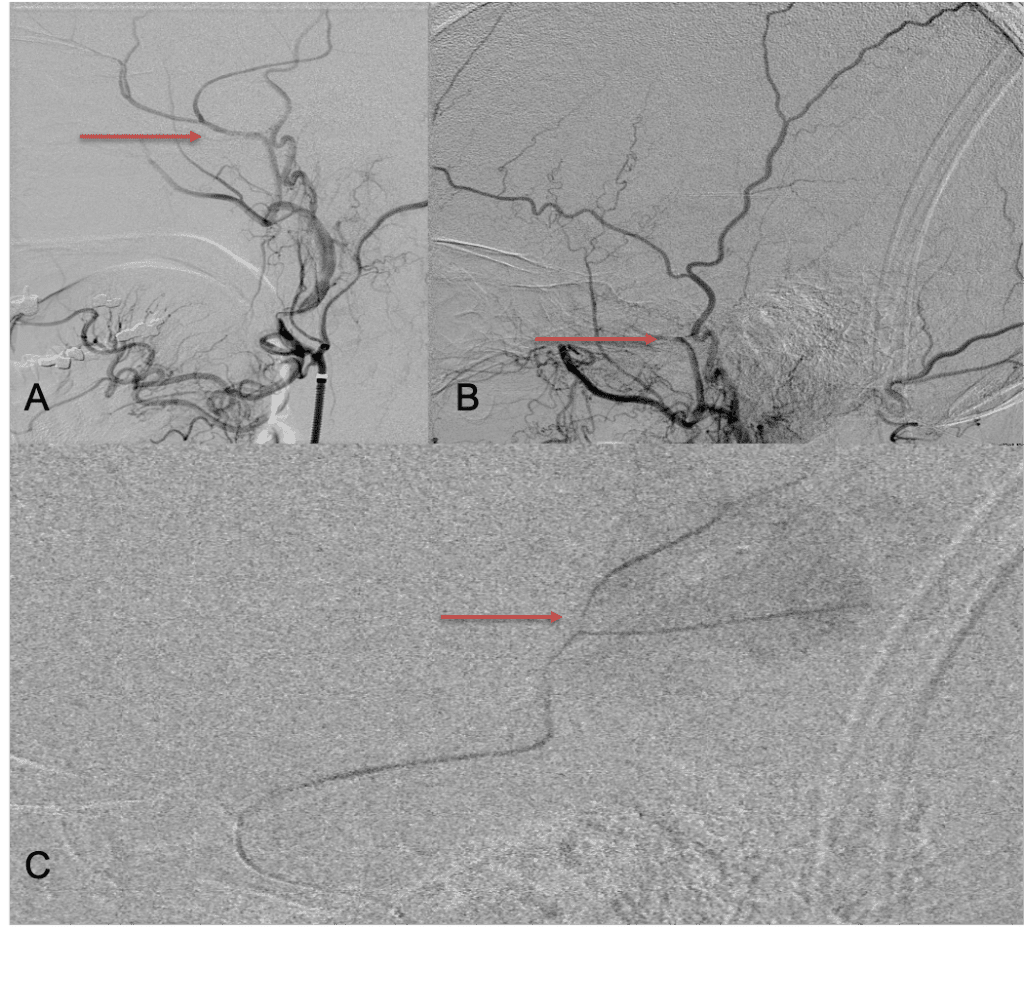

The patient agreed to receive minimally invasive treatment with Bilateral Middle Meningeal Artery Embolization, a new approach to promote resorption of chronic and subacute subdural hematomas in patients that are not improving with conservative measures or have contra-indications to surgical evacuation. Selective catheterization of the Middle Meningeal Artery is followed by transarterial embolization of the territory and inflammatory membranes that are felt to be secreting serosanguinous proteinaceous exceeding the capacity for resorption. MMA embolization was performed bilaterally in this patient. (Figure 2. A and B)

Figure 2. A) Initial right ECA angiogram ; B) Post MMA Embolization; C) Selective Embolization Of Middle Meningeal Artery Membranes using PVA particles (arrows).

Although conventional surgical methods, such as burr hole irrigation or observation in asymptomatic or minimally symptomatic patients have been the mainstay of treatment, middle meningeal artery (MMA) embolization has emerged as a promising adjunctive or alternative treatment. MMA embolization is a neuroendovascular technique which involves placing a microcatheter into the Middle Meningeal Artery, most commonly on the side of the cSDH (occasionally, bilateral embolization has been recommended for larger or bilateral collection. Embolization of both the anterior (frontal) and posterior (parietal) division is performed using a variety of embolic materials (liquid NBCA, Onyx, coils), although polyvinyl alcohol particles of <250 microns are most commonly used to achieve distal penetration and occlusion of the pre-capillary and capillary beds. The micro-leakage of blood and transudative proteinaceous inflammatory fluid in these inflammatory membranes is creating an imbalance in cycle of resorption and preventing resolution or promoting recurrence or growth of these cSDH collections and associated mass effect and midline shift.

Care must be taken to place the microcatheter within a safe position for embolization, with special attention to potential collateral branches to the orbit/eye via sphenoid or meningo-lacrimal branches (which may cause vision loss) or petrosal branches supplying the geniculate ganglion, the tympanic portion of the facial nerve, and often the trigeminal nerve via a branch coursing along the greater petrosal nerve. Once a safe position in the main trunk of the MMA, or superselectively in each of its divisions is achieved, embolization is performed until stasis of contrast and dense contrast staining of the dura is observed within the embolized vascular beds.7

Figure 8. Dense contrast staining of vascular membranes during embolization.